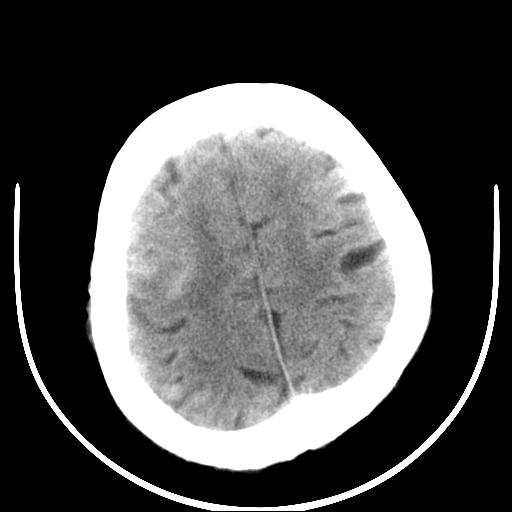

标题: CT16838:男58岁,意识不清2小时,请会诊出血部位该如何写。 [打印本页]

标题: CT16838:男58岁,意识不清2小时,请会诊出血部位该如何写。

呵呵  这样的做ct效果也太差了吧1首先 看见脑室扩大 1、左侧壳核出血。不足以解释临床的昏迷。

2、脑干区血肿。建议摆正位置 再来一次

图像质量太差,真不好确定,左基底结出血应该没有问题,再有就是蛛网膜下腔和脑干是否有出血,请老兄建议你们领导换机器吧

1)脑干、左侧桥小脑臂及小脑蚓部出血破入蛛网膜下腔。2)左侧基底节区灶性出血,不排除钙化灶。3)脑室系统少量积血。4)脑积水。

(患者病情危重,出现不自主运动——是引起图像质量不佳的主要原因)

脑干左侧原发性脑出血破入脑室系统及蛛网膜下腔出血伴梗阻性脑积水。左侧基底节区原发性脑出血。脑萎缩。

脑干左侧原发性脑出血破入脑室系统及蛛网膜下腔出血伴梗阻性脑积水。左侧基底节区像是钙化灶。轻度脑萎缩。

脑干左侧原发性脑出血破入脑室系统及蛛网膜下腔出血伴梗阻性脑积水。左侧基底节区原发性脑出血可能性大,钙化不除外。